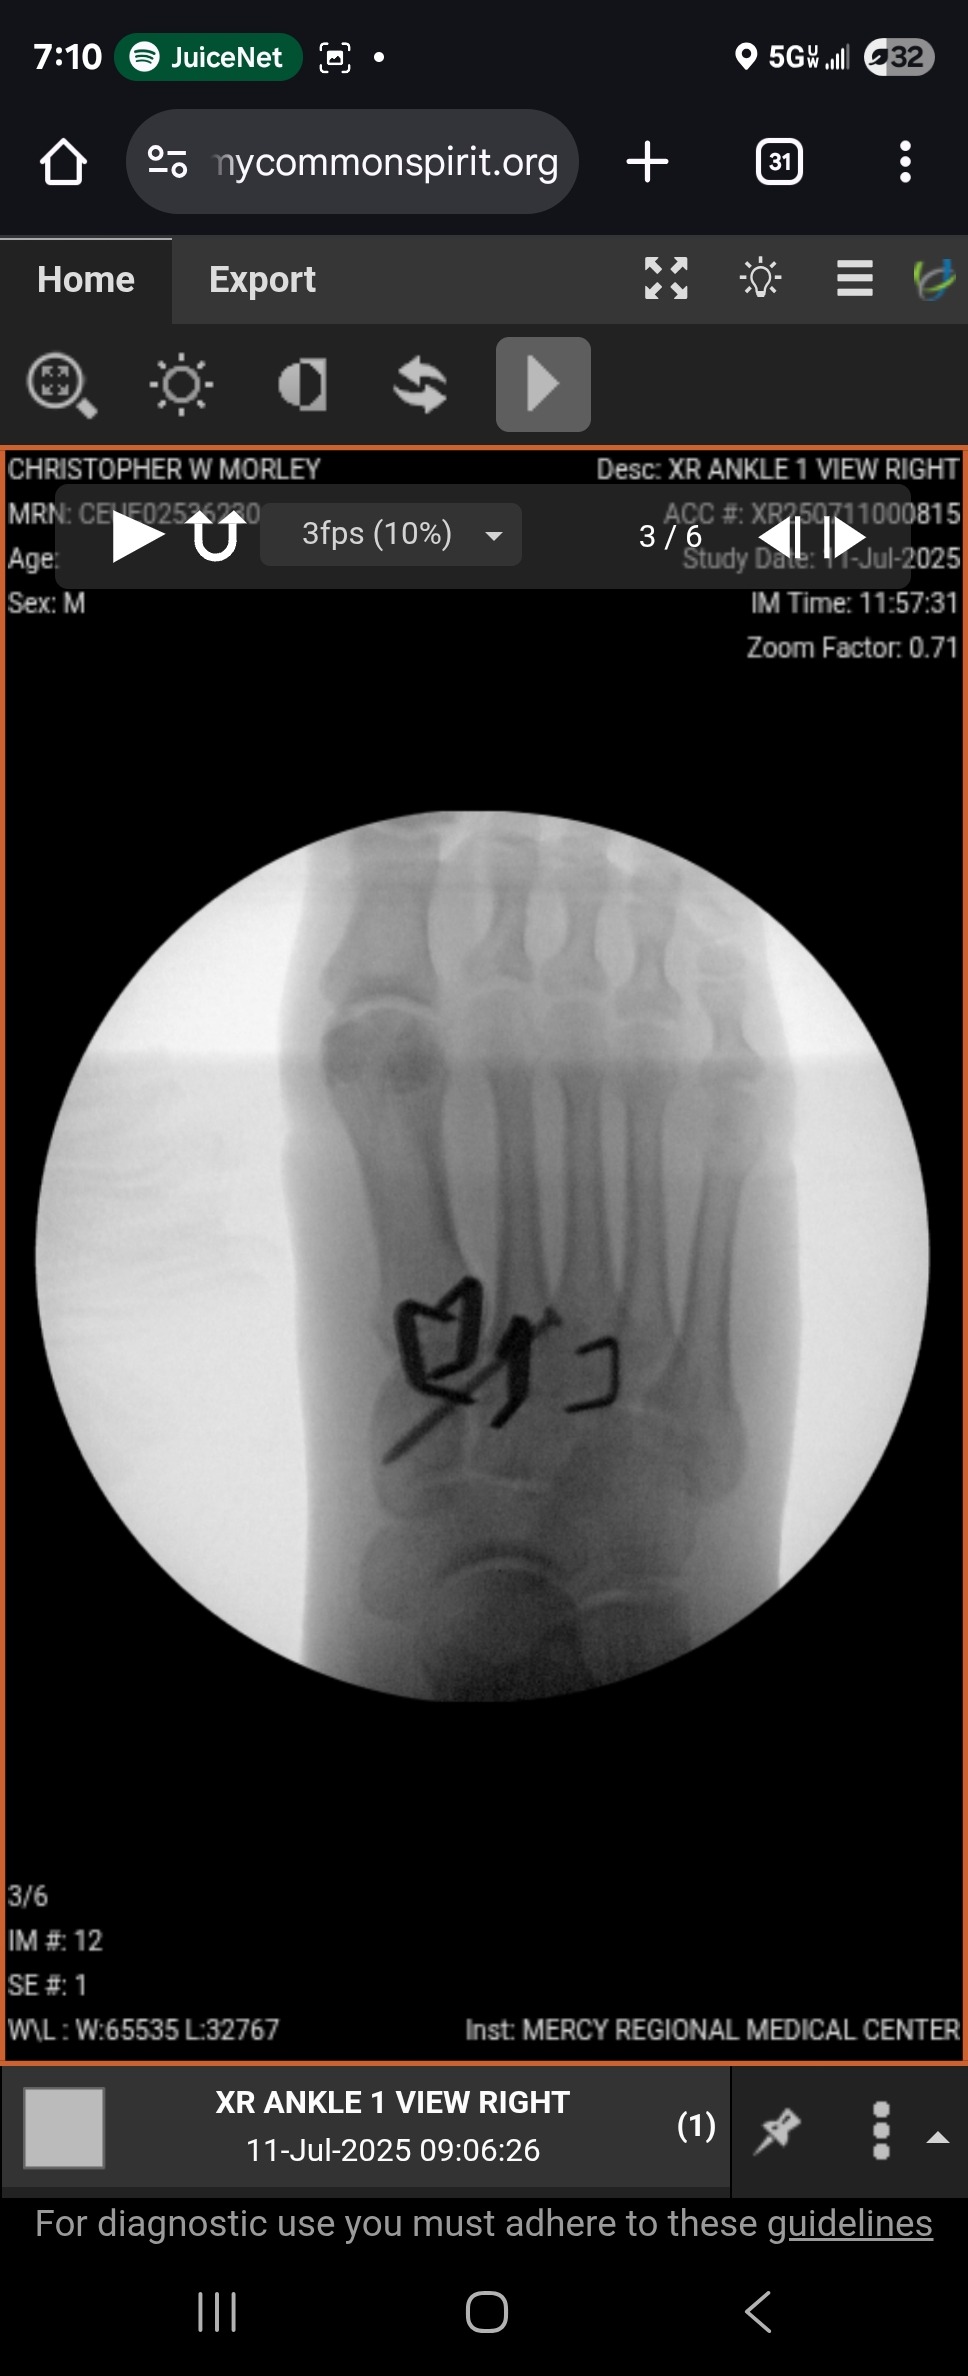

On 6/30 I was in a motorcycle accident. In the middle of a (amicable) divorce, I did something for me and it backfired; I traded some stuff for my first motorcycle. A low-speed fall on my first ride, the foot peg dug into my foot and scrambled my bones. Four out of five metatarsals were dislocated and a midfoot bone was crushed. $121K worth of surgery later, including a bone graft and several pieces of metal in my foot along with a screw, I'm in recovery.